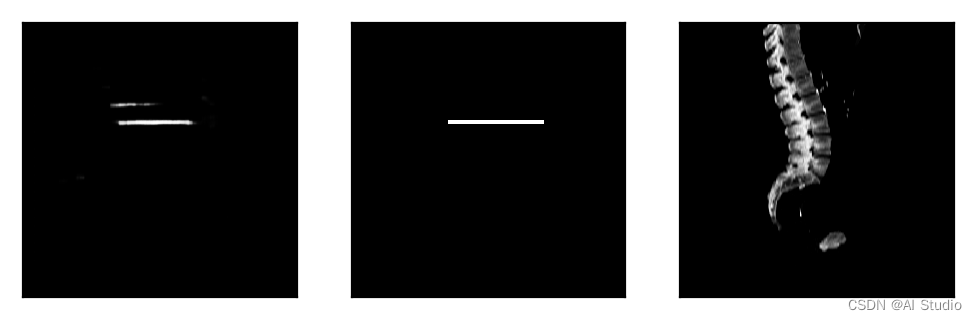

对读取数据集进行展示。

dataset = MRILocationDataset(images_frontal, images_sagittal, slice_locations,mode='train',k_fold=2)

print('=============train dataset=============')

for item in dataset:

images_frontal_ ,images_sagittal_,slice_locations_,label= item

print(slice_locations_,images_frontal_.shape,images_sagittal_.shape,label.shape)

break

images_frontal_ = np.squeeze(images_frontal_[0,:,:])

images_sagittal_ = np.squeeze(images_sagittal_[0,:,:])

label = np.squeeze(label)

imga = Image.fromarray(images_frontal_*255)

imgb = Image.fromarray(images_sagittal_*255)

imgc = Image.fromarray(label*255)

plt.figure(figsize=(6, 2))

plt.subplot(1,3,1),plt.xticks([]),plt.yticks([]),plt.imshow(imga)

plt.subplot(1,3,2),plt.xticks([]),plt.yticks([]),plt.imshow(imgb)

plt.subplot(1,3,3),plt.xticks([]),plt.yticks([]),plt.imshow(imgc)

plt.show()